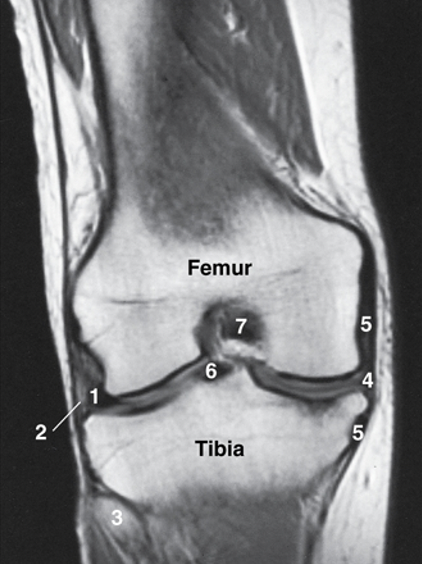

Label

A

1. lateral meniscus

2. LCL

3. head of fibula

4. medial meniscus

5. MCL

6. ACL

7. PCL